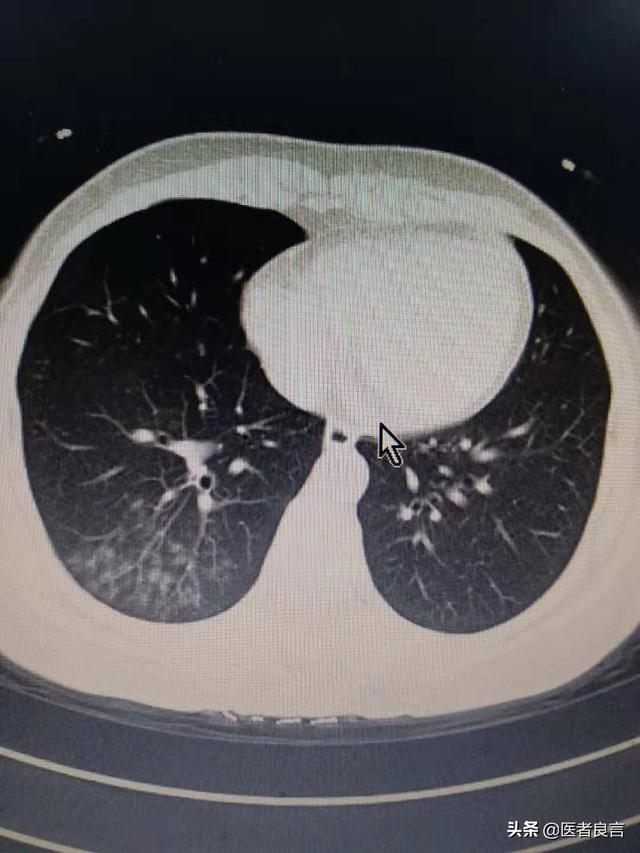

Les radiographies du thorax et l'imagerie par tomodensitométrie des poumons peuvent révéler des zones d'ombre inégales dans les poumons, qui sont évidentes dans les bandes extérieures des poumons, et dans les cas les plus graves, des zones d'ombre solides dans les poumons peuvent être observées.

2. avec des caractéristiques d'imagerie de pneumonie :Cela signifie qu'il y a des changements inflammatoires dans les poumons, présentant de multiples petites ombres en taches et des changements interstitiels, qui sont évidents dans les bandes externes des poumons, et même des changements tels que de multiples ombres en verre dépoli et des ombres d'infiltration dans les deux poumons. Vous vous demandez peut-être pourquoi il y a des changements d'imagerie dans les poumons après une infection. C'est principalement parce qu'une fois que le virus a envahi les poumons, il peut provoquer une congestion et un œdème dans les poumons, qui se traduisent par des ombres de haute densité sur la radiographie ou la tomodensitométrie.

②La tomodensitométrie thoracique peut suggérer de multiples ombres parcellaires et des changements interstitiels au stade précoce, et elle est évidente dans les bandes extrapulmonaires, et l'examen ultérieur développe de multiples ombres en verre dépoli et des ombres d'infiltration dans les deux poumons, et dans les cas sévères, des lésions pulmonaires solides apparaîtront.

②. Le thorax présente les caractéristiques d'imagerie d'une pneumonie.

Au stade initial, elle présente de multiples petites taches et des changements interstitiels, qui peuvent évoluer vers de multiples taches en verre dépoli et infiltrées dans les deux poumons et, dans les cas les plus graves, des changements solides dans les poumons peuvent se produire, ce qui donne ce que l'on appelle communément les "poumons blancs".

2. la tomodensitométrie des poumons montre des ombres en verre dépoli ou infiltrantes (une ombre blanche des poumons sur le film de tomodensitométrie).

Cet homme d'âge moyen, qui toussait et avait de la fièvre depuis trois jours, présentait au scanner une pneumonie inférieure gauche, répartie le long du sous-segment, avec une densité relativement élevée (pas d'ombre de verre dépoli), et des signes d'insufflation bronchique étaient observés du côté hilaire des poumons, accompagnés d'une augmentation de la numération sanguine, ce qui en faisait une pneumonie banale, et non un coronavirus.